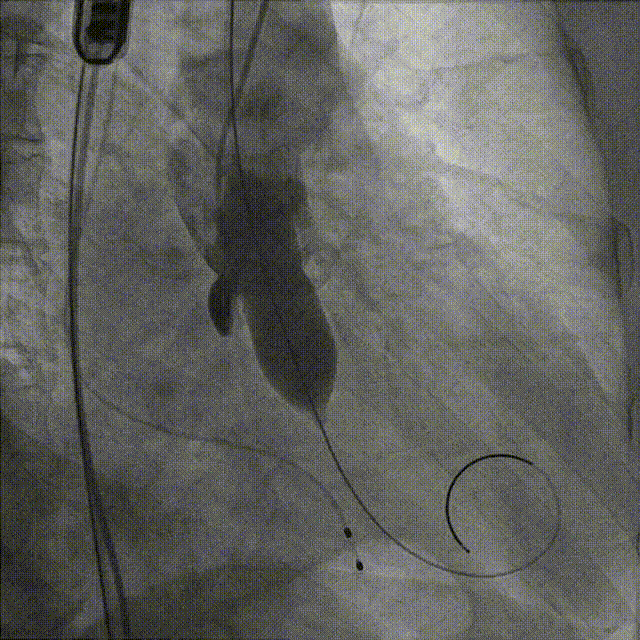

术中先行冠脉造影检查,前降支中段有明显狭窄,随即先行PCI治疗,植入冠脉支架。

主动脉根部造影,显示瓣叶增厚,伴有明显返流。

选择22mm球囊进行预扩,结果显示具有明显腰征,无瓣周返流,随即选择TaurusElite26mm瓣膜,凭借其优异的柔顺性,轻松完成过弓。